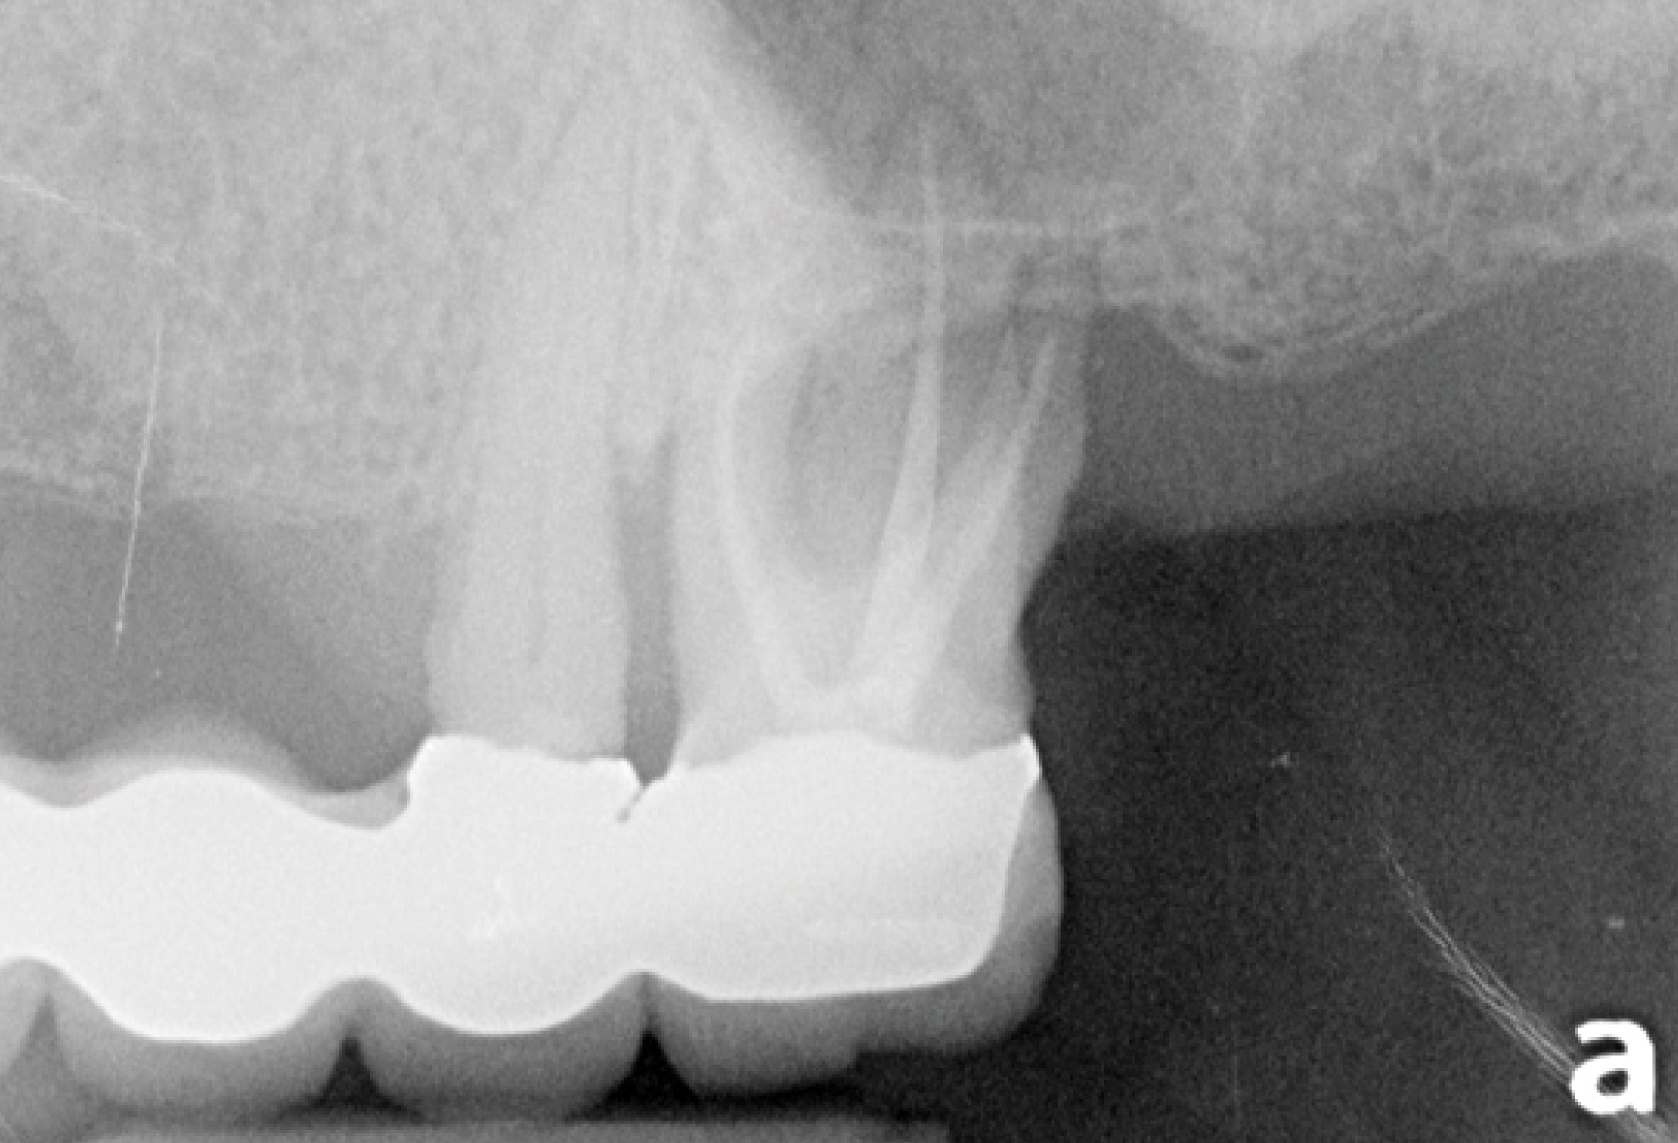

Topic 2

Endodontic diagnosis for everyday practice

Endodontics

● Understanding the basic sciences in relation to endodontic diagnosis

● This matters to aid during pre, mid and post operation pain management

● Important information when using medication as an adjunct to odontogenic pain management.